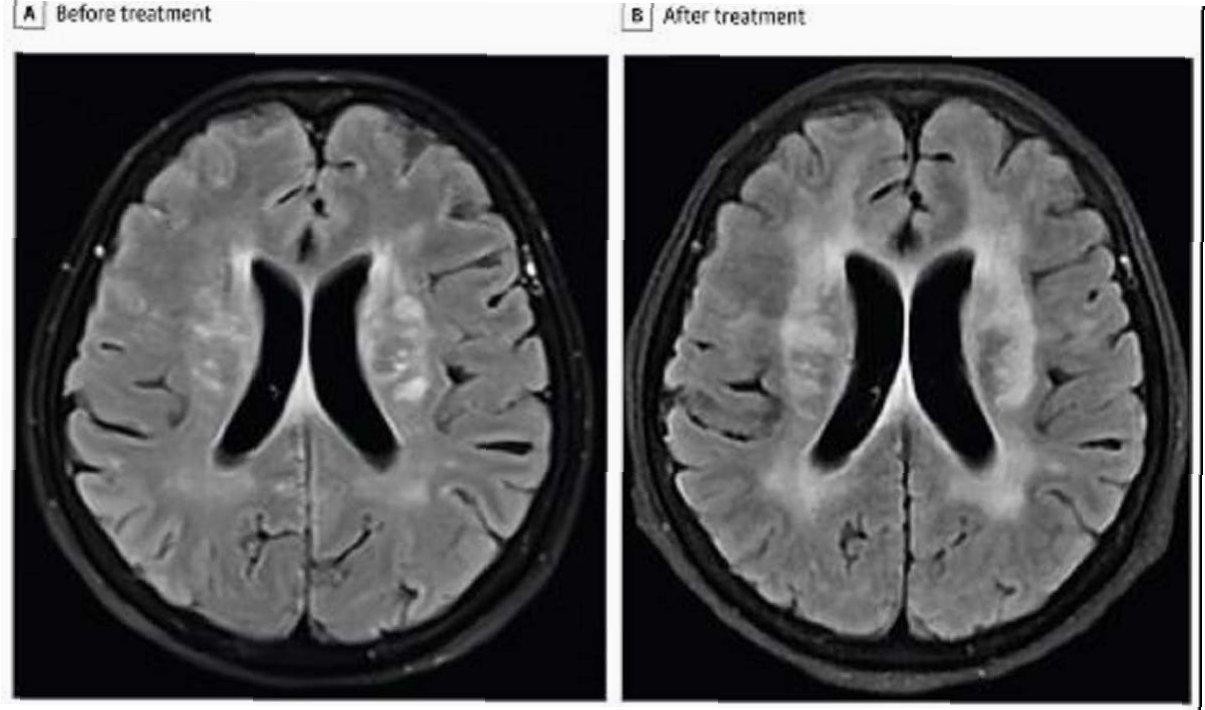

성공적인 치료와 회복 과정

뇌에서 기생충을 제거하는 수술과 함께 구충제 및 항염증제 치료가 병행되었습니다. 수술 후 6개월이 지나자 환자의 폐와 간 병변은 사라졌고, 백혈구 수치도 정상으로 돌아왔습니다. 또한, 신경정신과적 증상이었던 우울감과 기억상실도 호전되는 경과를 보였습니다. 이 성공적인 치료 사례는 희귀 기생충 감염의 진단과 치료에 대한 중요한 정보를 제공합니다.